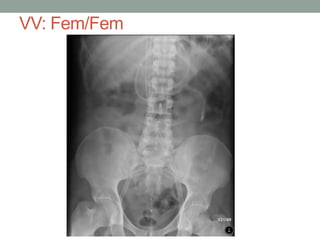

VV: Fem/Fem

Severe Blunt Chest w/ TBI